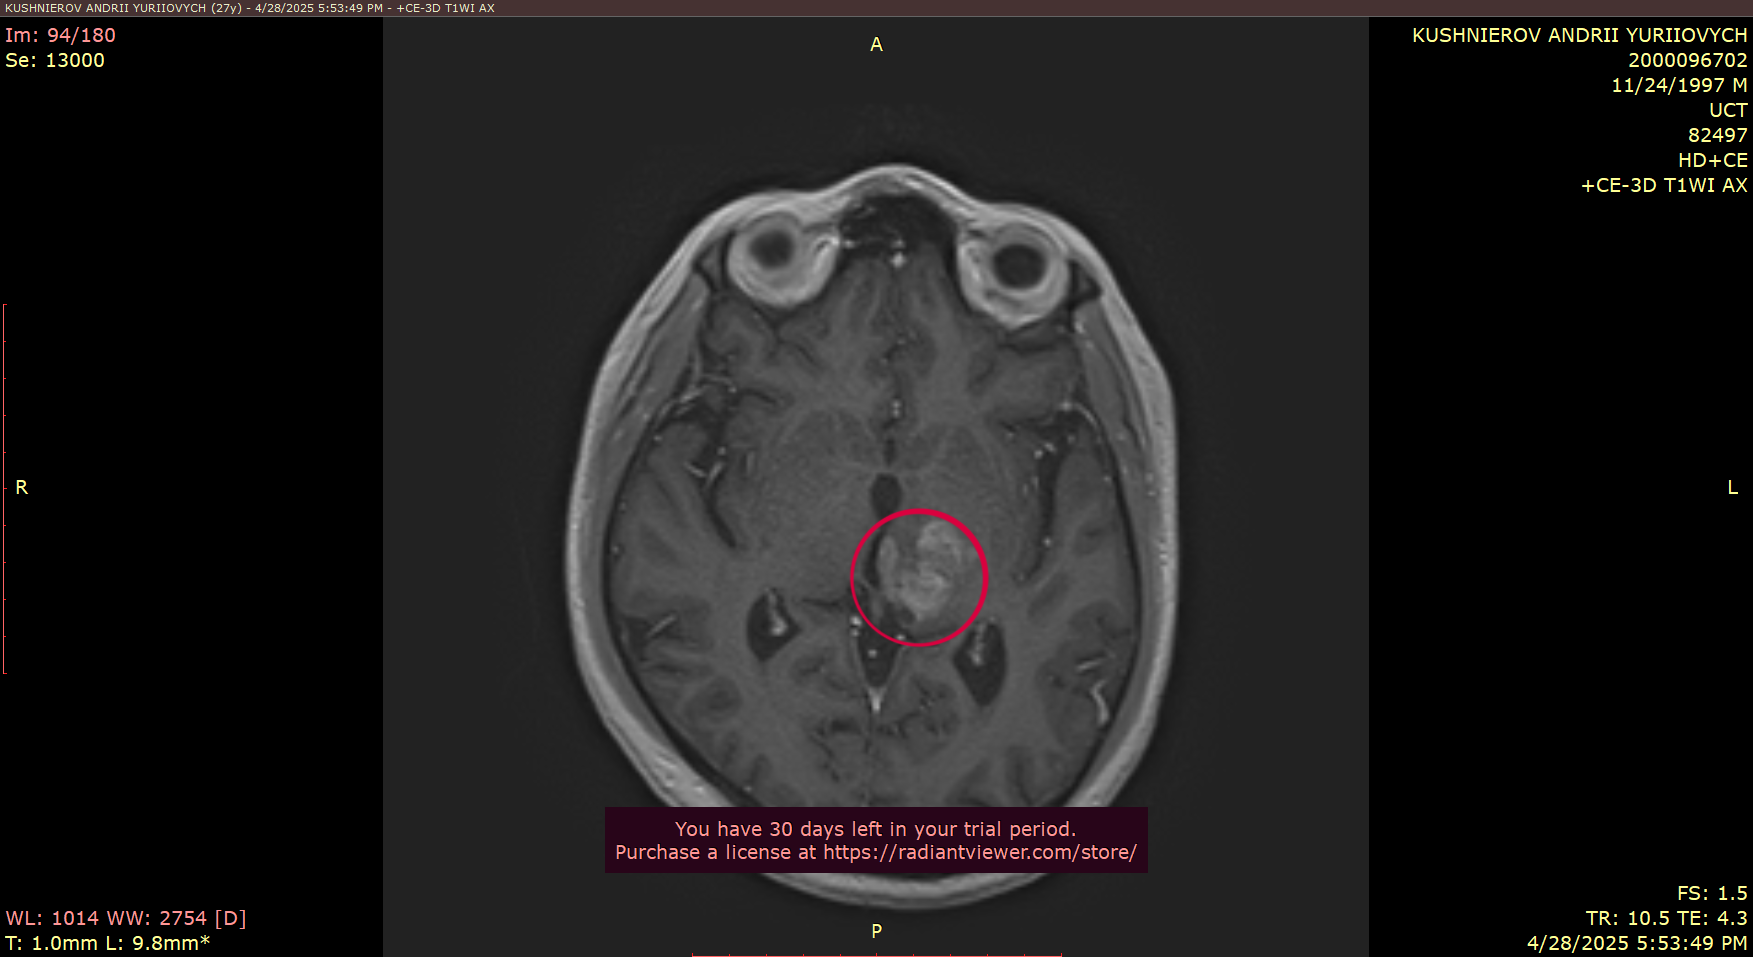

As some are aware - he was diagnosed last year with glioblastoma, an aggressive cancer of the brain and many in the community helped to fund his biopsy.

As many of you know, I’ve been battling glioblastoma — an aggressive form of brain cancer. Over the past year, I underwent 12 months of chemotherapy, hoping it would stop the tumor’s growth. Unfortunately, it hasn’t helped. The situation has become critical.

The location of the tumor in the brain makes the tumor almost inoperable, because of the high risk of being paralyzed — but now my condition has worsened, and emergency brain surgery must be done very soon, likely next week, here in Ukraine to address the immediate threat. This surgery won’t heal me, but it’s necessary to stabilize my condition. After that, I must travel to Germany for more advanced treatment and another surgery, which may allow doctors to remove a larger portion of the tumor and offer a better chance at extending my life.

Description of MRI scan results. Scan images are included above.